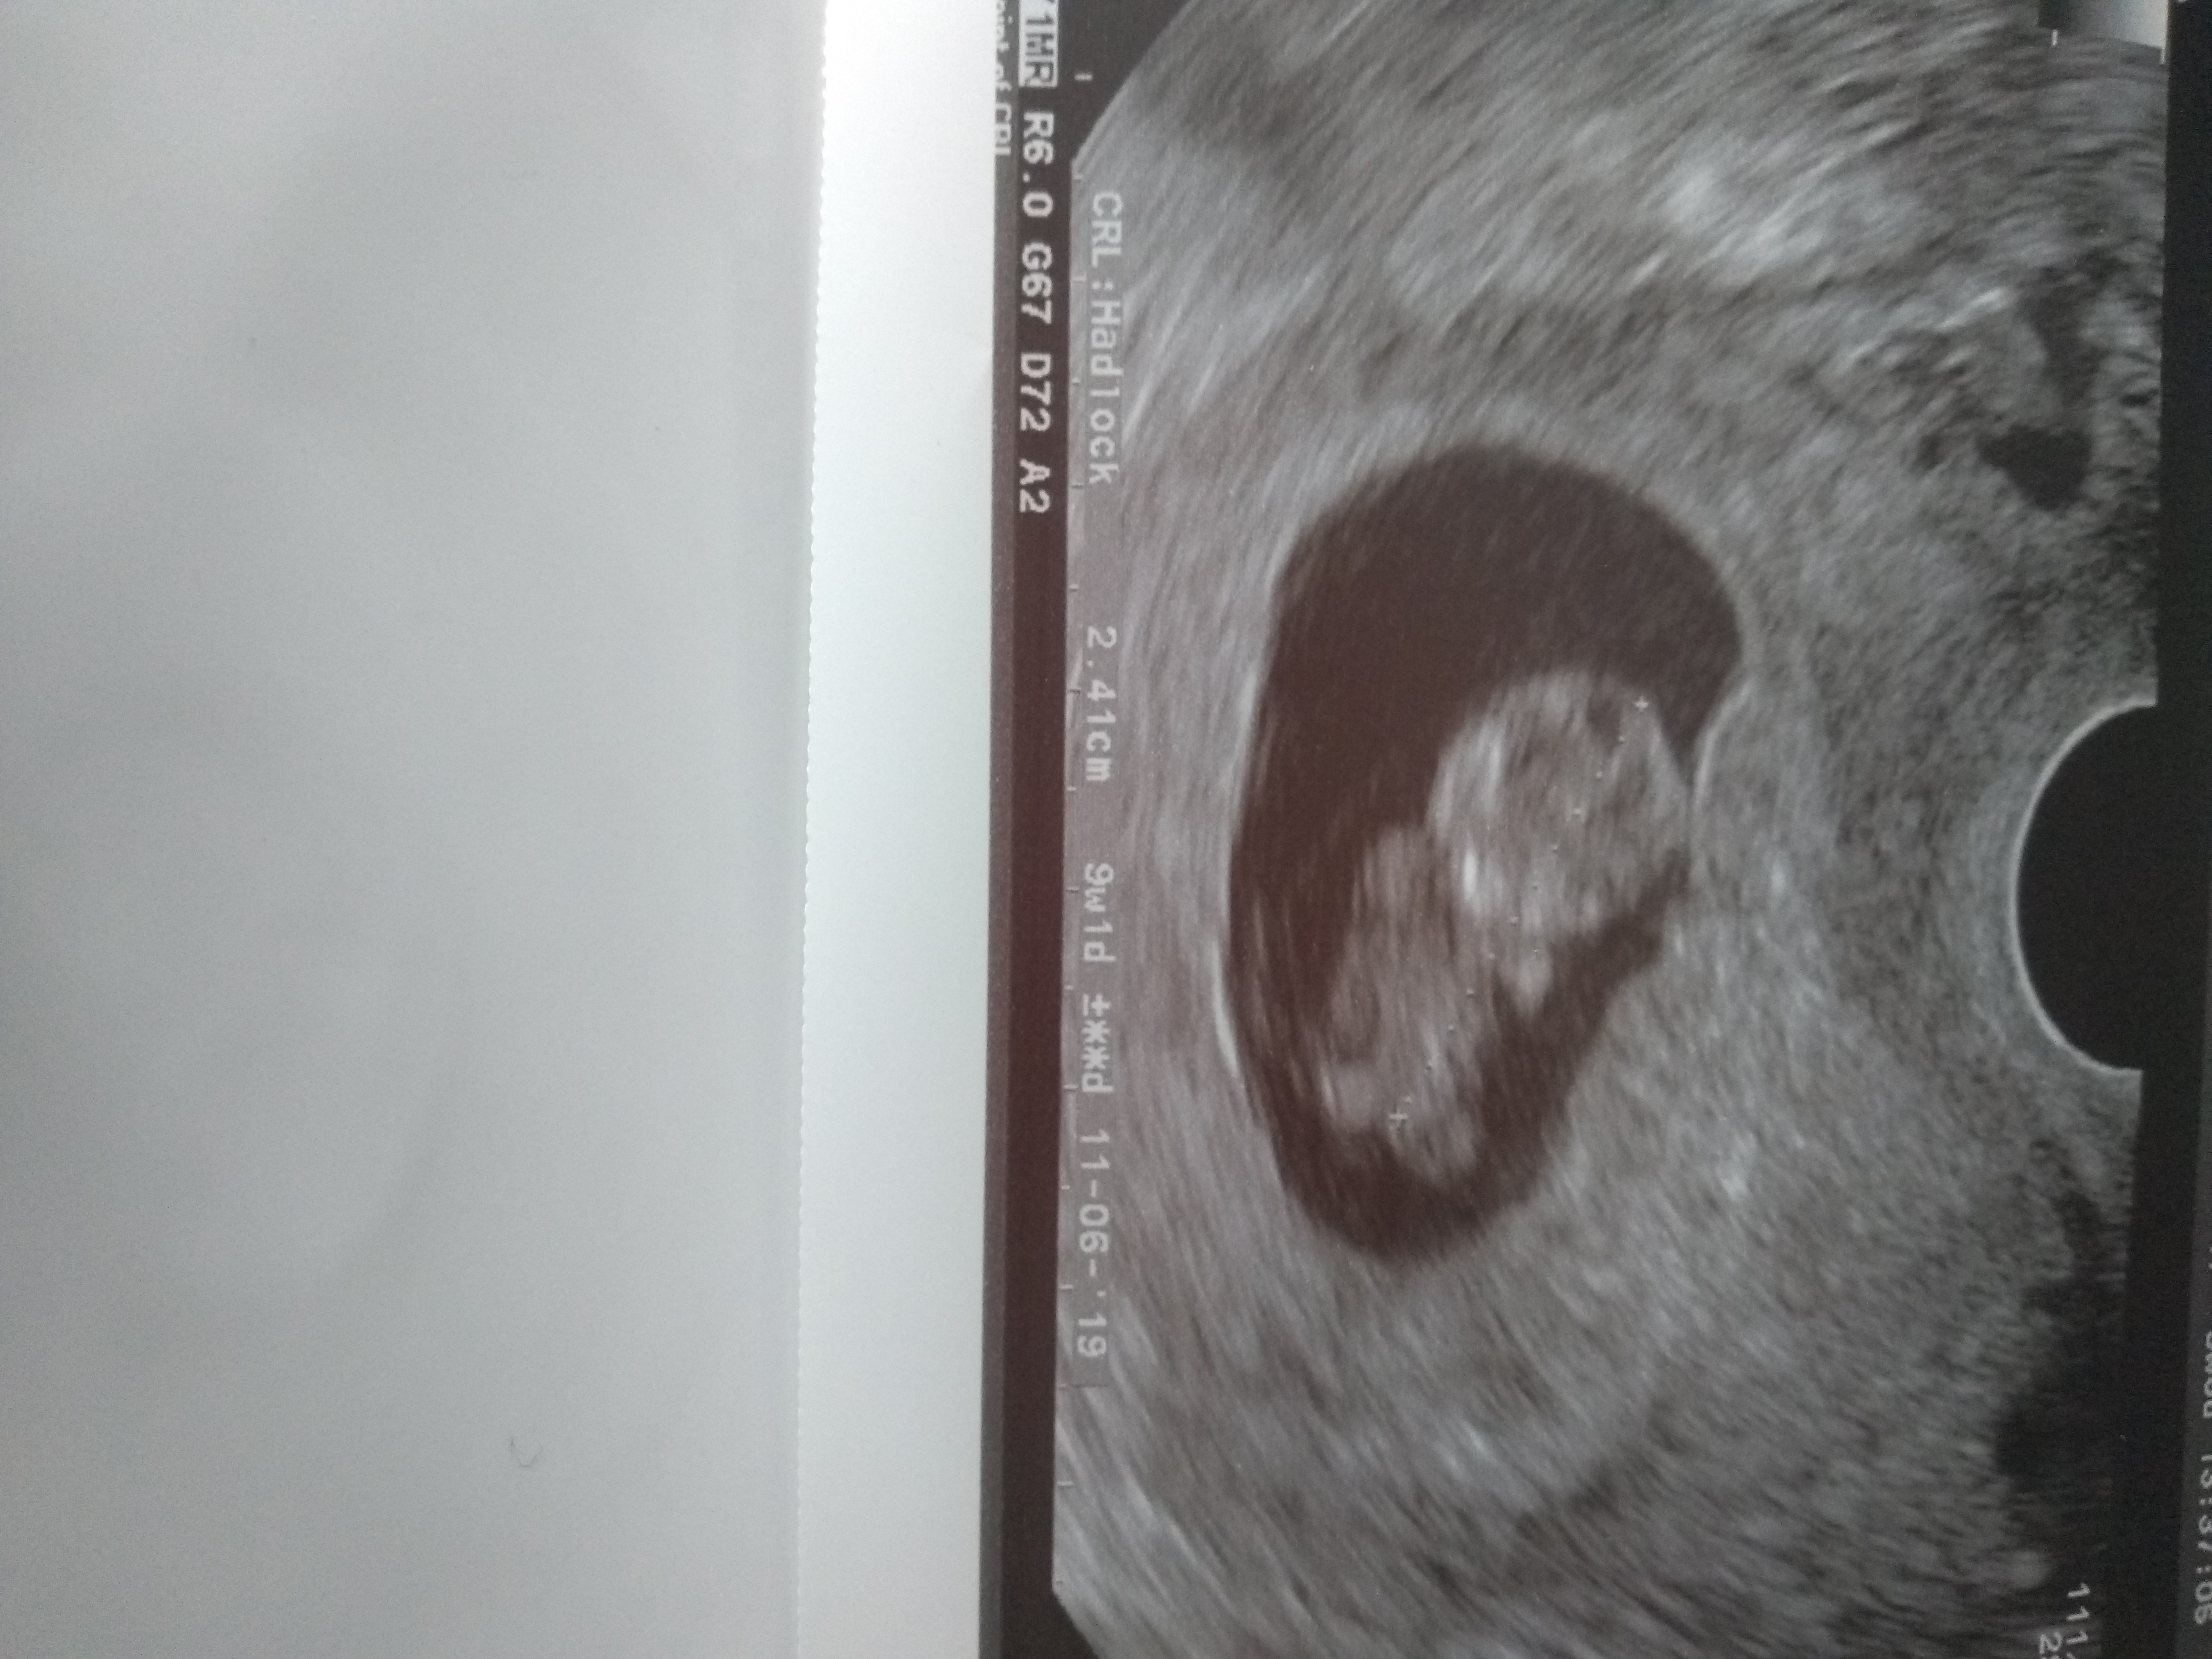

Melduje się po wizycie, wszystko jest ok . Żadnych krwiakow ani nic złego się nie dzieje. Maluszek rośnie jak na drożdżach. Ma już 2,41 cm :) Zobacz załącznik 914502